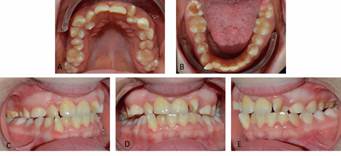

Mujer de 16 años con condición de Síndrome de Down. La madre consulta en la Clínica de Cuidados Especiales XXXXX (Ciego*) por apiñamiento dentario. La familia refiere mal comportamiento previo, historia de caries y cepillado irregular. Al examen físico general presenta discapacidad cognitiva moderada, hipotiroidismo, enfermedad celíaca y sobrepeso (Figura 1).

El diagnóstico integral con enfoque de riesgo es paciente género femenino, 16 años, potencialmente cooperadora, sin riesgo social, con riesgo biológico general, dentición permanente, gingivitis generalizada asociada a condición sistémica, lesión compatible con fibroma irritativo en flanco lingual izquierdo a nivel de 3.7. (Figura 2), caries oclusal profunda en diente 4.7, clase III esqueletal, biotipo braquifacial, perfil anterior anteinclinado, clase III canina y molar bilateral, overjet y overbite disminuidos, persistencia de dientes 5.3, 6.3 y 8.3, caninos permanentes con anomalía de tamaño por diente pequeño, apiñamiento dentario severo en maxilar y moderado en mandíbula, líneas medias dentarias no coincidentes, dinámica mandibular normal, respiración mixta, incompetencia labial, anteposición de cabeza. Se determinó la persistencia de tres caninos temporales, pero debido a la alteración de forma de los caninos definitivos se cuantificó éstos últimos como supernumerarios (Figura 3).